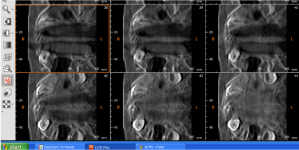

Initial CBCT images (Figure 1)

OPT (Figure 1): all permanent teeth are present but their eruption is delayed – there are some decayed teeth and some deciduous roots fragments – the tooth 3.5 is already erupted (other inferior bicupids and canines are not erupted) – the upper right bicuspids are erupted ( the left ones are not erupted yet) – the tooth 1.3 risks to be impacted, due to its inclination and mesial position – the tooth 2.1 is 90° rotated along its axis – the tooth 2.3 is transposed on the root of the tooth 2.2, which is horizzontally laying near bicuspid roots (Figure 2).

Figure 1. INITIAL OPT

Figure 2. CROSS SECTIONS SHOW 2.1 ROTATED, 2.3 TRANSPOSED ON 2.2 LAYING